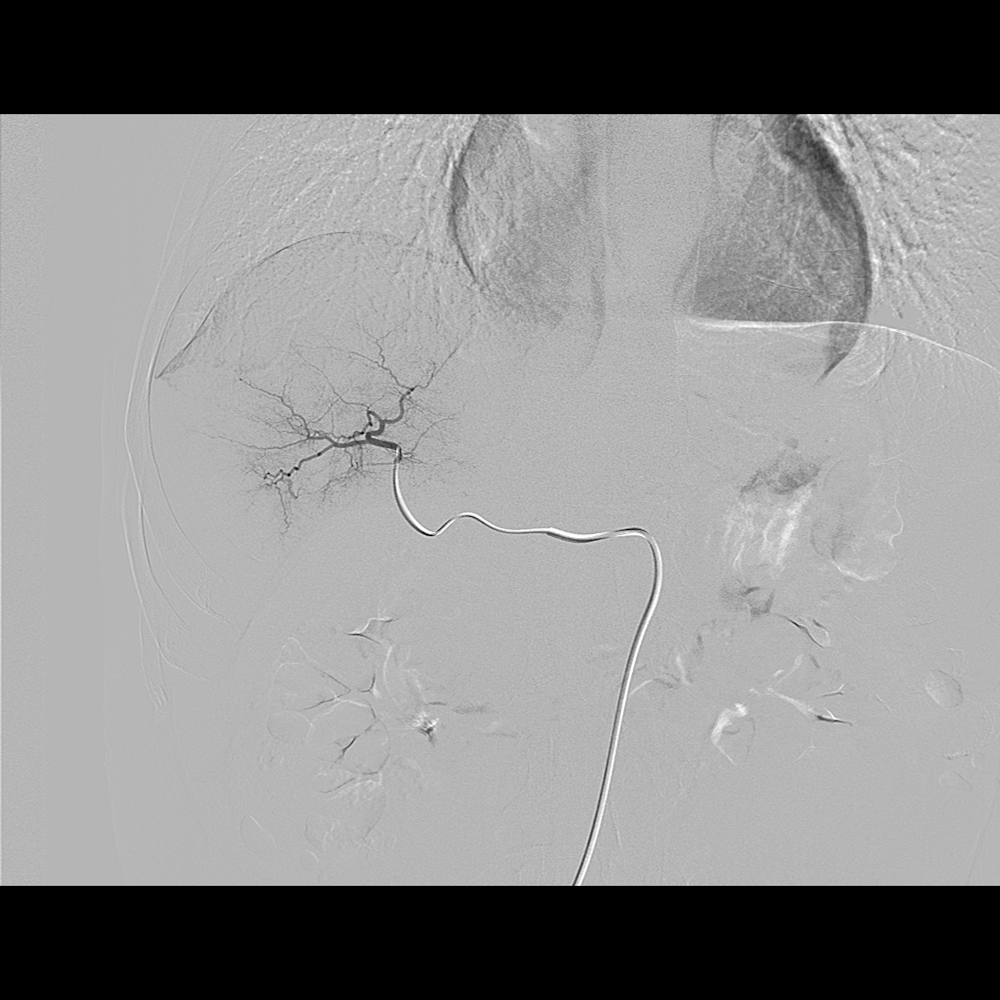

2.外周血管介入手术治疗:腹主动脉血管病症,肝脏肿瘤治疗,肝脏,肺部肿瘤活检,椎体成形术,泌尿系统血管病变等微创介入手术。

DSA造影显示肝癌 通过微导管栓塞病灶,阻断了肿瘤供血,肿瘤逐渐萎缩